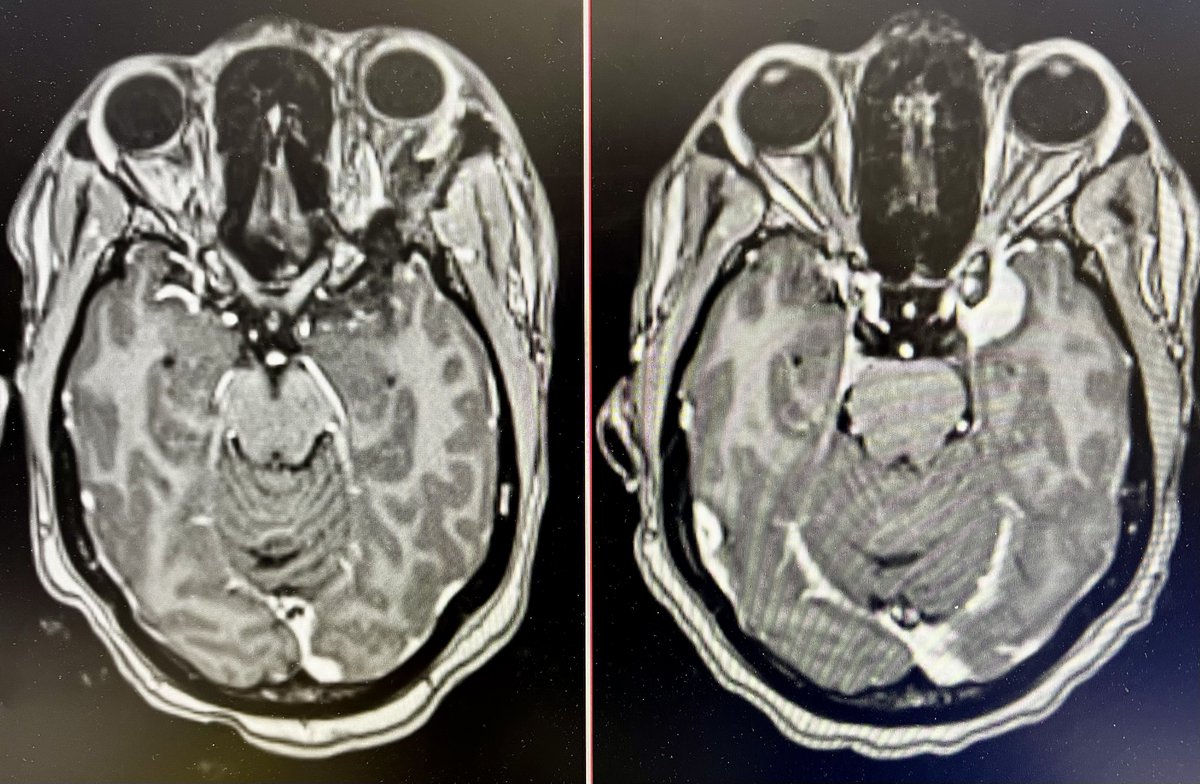

During Brain Tumour Awareness Week, we want to acknowledge your donations that helped fund brain cancer research at Leeds Teaching Hospitals NHS Trust. In 2021, we granted £200,000 to Christopher Fudge's research on glioma cells and tumour recurrence after surgery.

Late breaking at #ASCO23: Mutations in isocitrate dehydrogenase 1 or 2 are common in low-grade glioma. The IDH inhibitor vorasidenib improved progression-free survival as compared with placebo. Full results of the INDIGO trial: nej.md/3N8N5dU